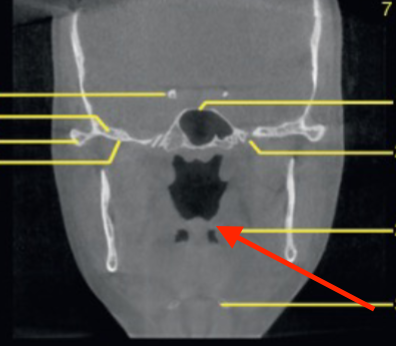

coronal

what plane is this slice

what plane

posterior of maxillary sinus

where is this slice

mental foramen (at premolar region)

identify the structure

mandibular canal/inferior alveolar canal

what is the ARROW pointing to

orbital roof

what are the arrows pointing to

nasal floor

identify the structure indicated by the ARROW